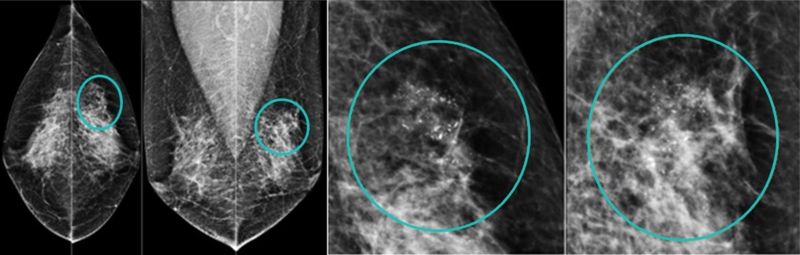

56歲王小姐,在國健署免費乳房攝影篩檢後發現:左乳房外上方有一群聚微鈣化點,經手術證實為乳癌初期,後續恢復良好。

國際公認最有效的篩檢工具,偵測乳房內「微鈣化點、局部組織變形」。台灣研究顯示:每2年接受1次乳房攝影檢查,可降低乳癌死亡率41%、減少30%的第二期以上乳癌發生率。目前國健署補助45~69歲、40~44歲二等親內有乳癌家族史女性「每2年一次免費乳房攝影檢查」,婦女應多加利用。但乳房攝影對亞洲女性高比例的緻密型乳房(高比例乳腺組織),診斷率較差,可合併「乳房超音波」檢查,以減少檢查盲點,增加診斷率。